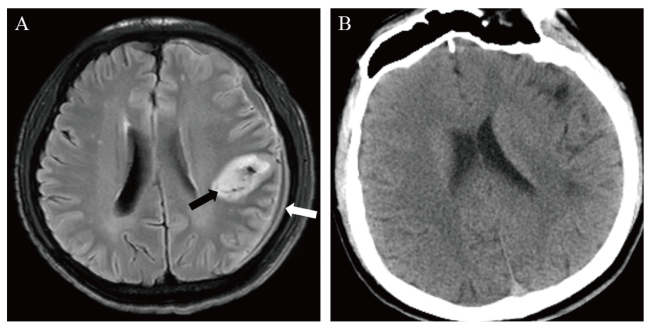

入院影像学检查:肺部CT提示双肺内多发斑片状影,考虑为肺部感染。颅脑CT提示左侧额顶部骨质内板下新月形稍低密度影,CT值约29 Hu,邻近脑实质受压、脑沟变浅,左侧侧脑室受压缩小,左侧额叶内结节状高密度影,周围未见水肿(图1A)。颅脑MRI提示左侧额顶部骨质内板下新月形异常信号影,其内可见液-液平面,其腹侧呈低T1加权像(T1WI)、高T2WI信号影,T2液体抑制反转恢复序列(FLAIR)呈低信号影,其背侧呈等T1WI、稍高T2WI信号影(图1BC),弥散加权成像(DWI)可见新月形异常信号背侧部分弥散受限(图1D),表观弥散系数(ADC)值约为774×10-6 mm2/s,增强扫描左侧额顶部硬脑膜明显强化,左侧额顶叶软脑膜轻度强化(图1EF)。

图1 一例艾滋病合并伤寒沙门菌感染致硬膜下脓肿患者入院影像学检查结果

注:检查时间为2020年9月22日。A为颅脑CT平扫,示左侧额顶部骨质内板下新月形稍低密度影(白箭头);B、C为颅脑MRI平扫T2WI及T1WI,示左侧额顶部骨质内板下新月形异常信号,其内可见液-液平面(白箭头);D为DWI,示新月形异常信号影背侧部分弥散受限;E、F为颅脑MRI T1WI增强矢状位及冠状位重建,示左侧额顶部硬脑膜明显强化(白箭头),左侧额顶叶软脑膜轻度强化(黑箭头)。